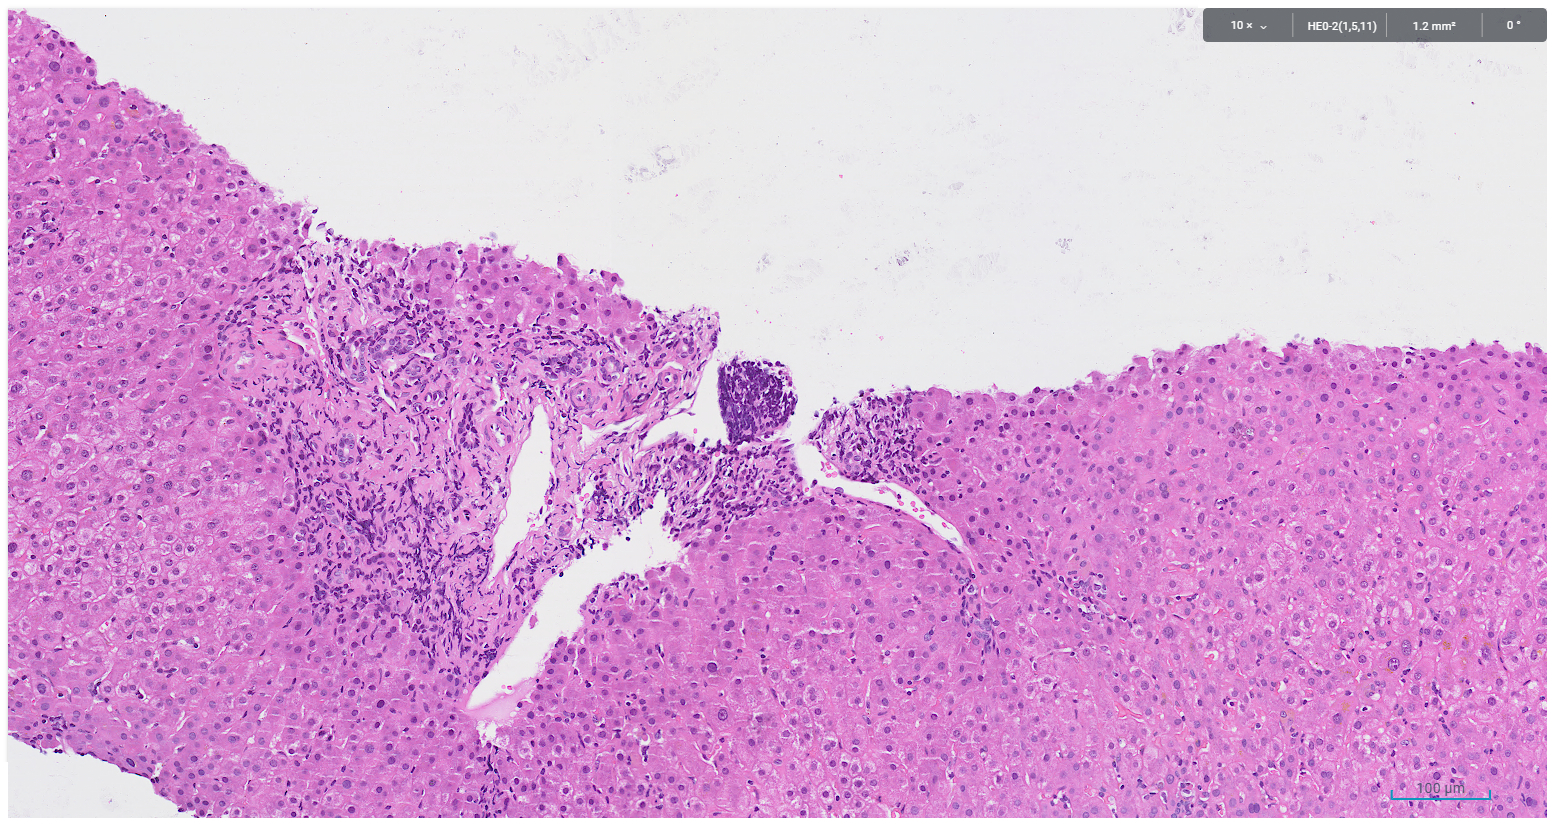

A core biopsy taken from the right hepatic lobe showed periportal chronic inflammation without a prominent plasma cell component, and focal interface activity (Figure 1). Mild bile ductular proliferation and mild periportal fibrosis were noted and highlighted with CK7 immunohistochemistry (Figures 2 and 3). There was no evidence of bile duct injury or ductopenia. The hepatic lobules contained scattered chronic inflammatory infiltrate and mild canalicular cholestasis (Figures 4 and 5). Steatosis, confluent necrosis, Mallory-Denk bodies and granulomata were not identified.

Figure 2. Bile ductular reaction, periportal fibrosis and chronic inflammation devoid of plasma cell infiltrate